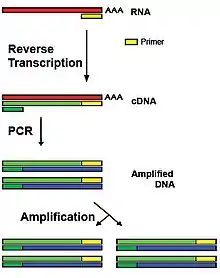

Colorado tick fever virus can be detected in a patient with a reverse transcription polymerase chain reaction (RT-PCR), where even a single virion and its genetic material can be detected.[7] The antigens to the virus can also be detected using immunofluorescence.[5] There is currently no known vaccine or treatment available to treat these Coltiviruses, but 3'-fluoro-3'-deoxyadenosine, a nucleoside analog, halts replication of Colorado tick fever virus in vitro.[5]